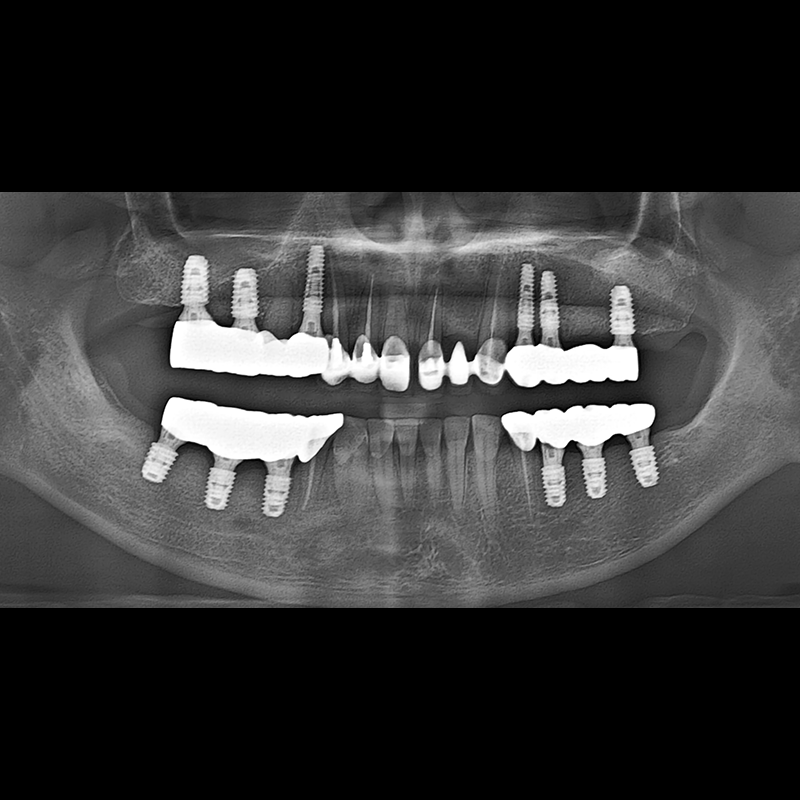

IMPLANT

BEFORE AFTER